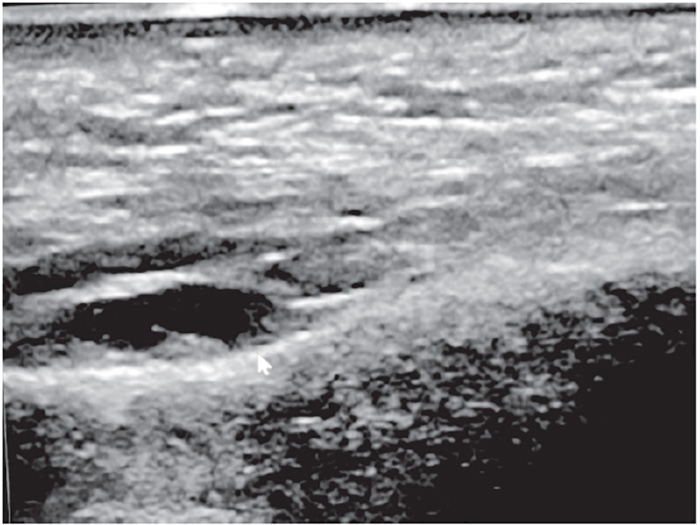

The highly hydrophilic nature of commercial HA gels provides an ideal acoustic appearance on ultrasound. HA acts like fluid, when properly hydrated, appearing anechoic to hypoechoic, with good acoustic transmission. HA does have a variable appearance dependent on filler viscosity, age, and degree of tissue biointegration [68]. Freshly injected HA may not have a significant acoustic footprint and can be imperceptible to normal tissue; it is only when hydrated/fluid-bound and hydrophilic that it appears anechoic to hypoechoic, particularly with highly viscous HA preparations [69]. Acoustic enhancement posteriorly is a property of HA and hydrophilic preparations. An example of supraperiosteal placement of hyaluronic acid filler is illustrated inFigure 3.

Of the two commonly used temporary cosmetic fillers available commercially, HA filler is the most widely recognized and used [93]. Hydrated HA filler has an anechoic to hypoechoic appearance (similar to simple fluid), and stands out as distinctly darker than surrounding tissues, such as skin, dermis, and muscle. Some heterogeneity within the filler could be encountered, depending on age and maturity of the filler, probably the result of biointegration into surrounding tissues [94].